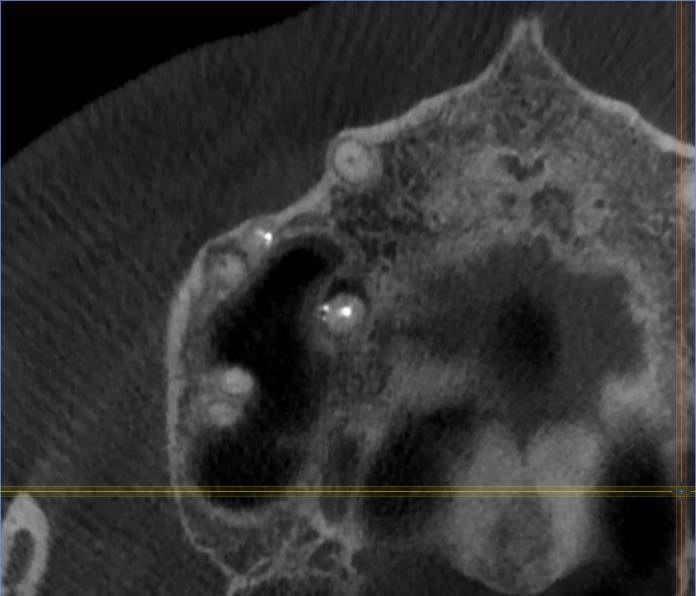

И есть второй зуб с проблемой около корней -16 (РФ зуб). Перед брекетами уже перелечивали корни в 2016 году.

Сейчас опять говорят надо заново перелечивать перед протезированием.

Имеет ли смысл? (а то так до бесконечности можно перелечивать и дешевле удалить было и имплантант поставить).16.jpg.c48b680915f979a9e4778f4248ff39c7.jpg16-1.jpg.c116f77ce054f4d184897797128c176a.jpg16-2.jpg.675bd02ec47e5582670209e0dc324a7f.jpg16-3.jpg.ece96fa59fc264e0e38c691000fc9780.jpg16-4.jpg.a269497c8968ad8cbd4d3c558c480d90.jpg16-5.jpg.e4f929dd96c9da3ce934b217da02a634.jpg16-6.jpg.260d3caac245b47f76f4f53ca38317c4.jpg